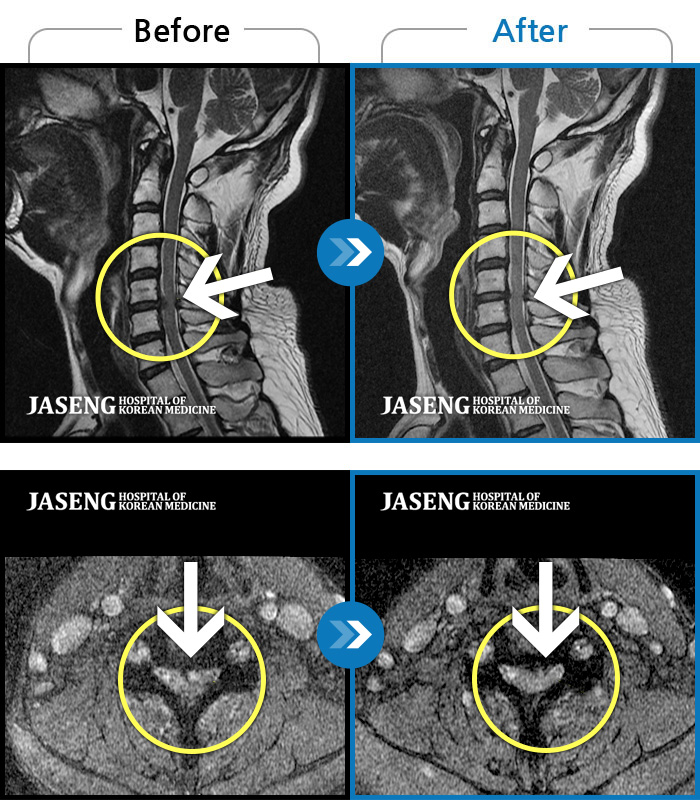

Before

After

환자에게 사전 동의를 받아 동일 조건에서 촬영되었습니다.

개인에 따라 치료 후 부작용이 발생할 수 있으니 의료진과 상담 후 치료를 진행하시기 바랍니다.

목 통증과 새끼 손가락 저림 및 안정시에도 우측 어깨 통증 호소하여 내원하셨습니다.